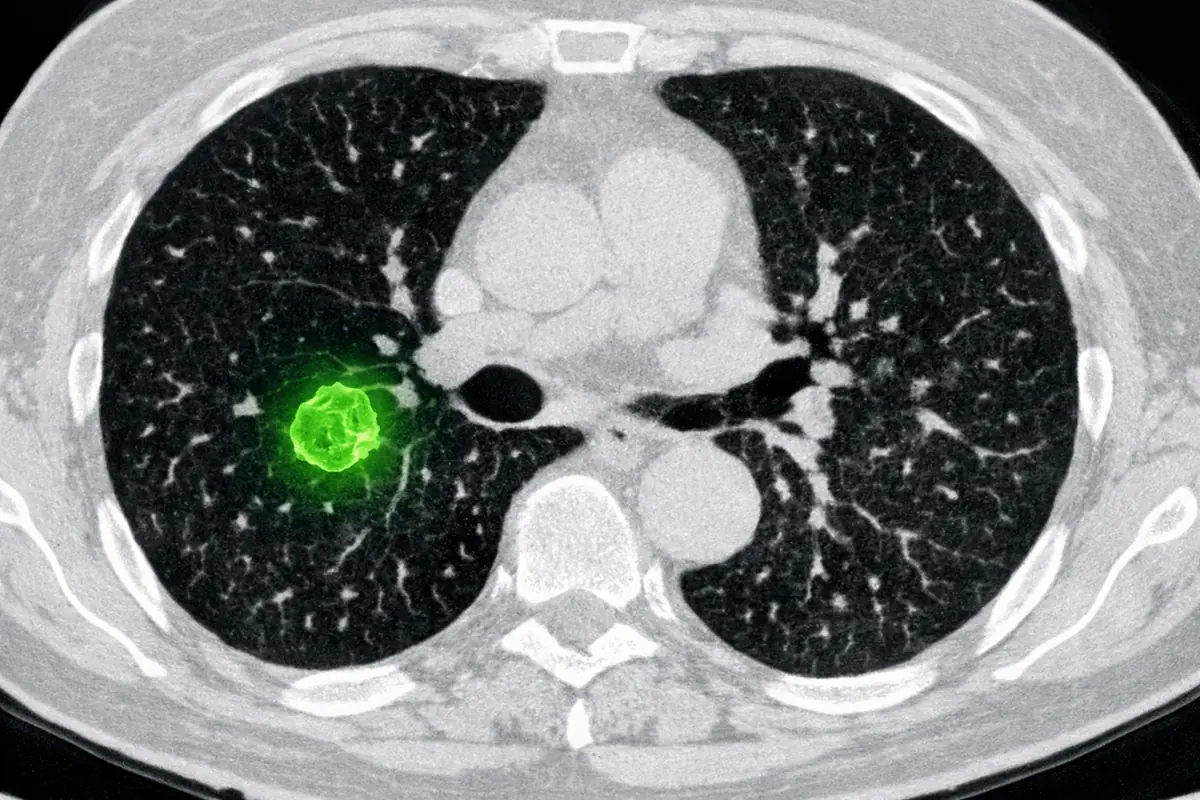

Le diagnostic médical assisté par IA est probablement l’application la plus avancée aujourd’hui. Des systèmes entraînés sur des millions d’images (scanners, IRM, radiographies) sont capables de détecter des anomalies que l’œil humain, même expert, peut manquer dans certaines conditions.

Scanner médical annoté par une IA, mettant en évidence une petite tumeur pulmonaire à un stade précoce.

Sur la détection précoce de certains cancers du sein ou du poumon, des études publiées ces dernières années montrent que des algorithmes atteignent une précision comparable, parfois supérieure, à celle de radiologues humains. Ce n’est pas une raison de retirer les médecins de l’équation. C’est une raison de les outiller différemment.